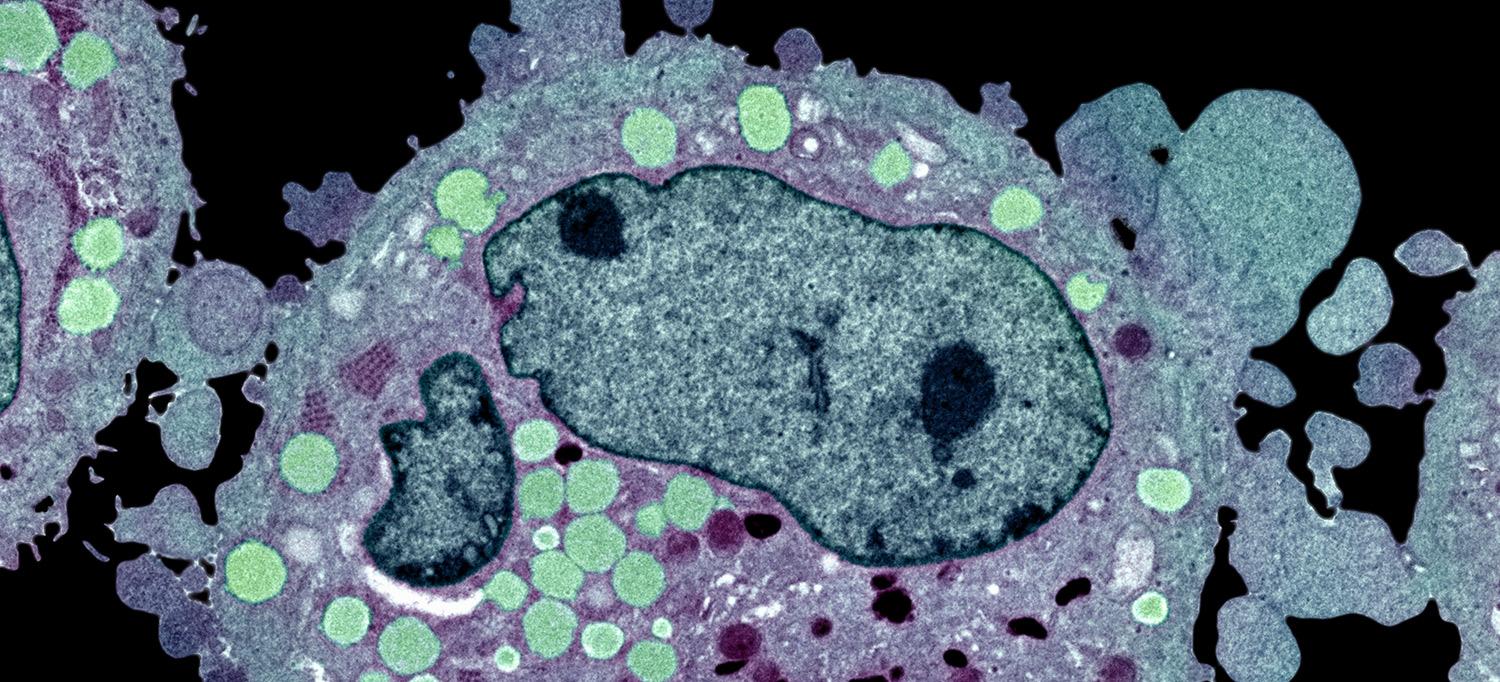

Photo: Science Photo Library - STEVE GSCHMEISSNER/Getty